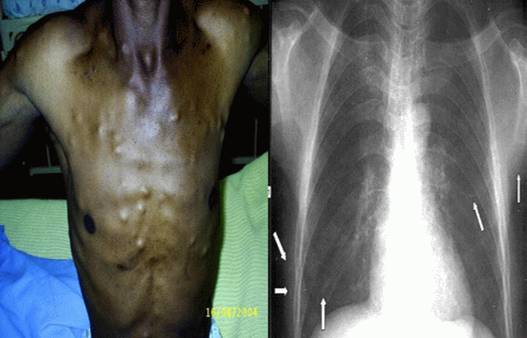

Ấu trùng sán lợn hay nhiễm sán dây lợn hiện đang gia tăng và là vấn đề y tếquan tâm tại Mỹ, đặc biệt ở khu vực tây nam và một số vùng khác có sự di cư nhiều của người dân đến các vùng lưu hành bệnh hoặc quần thể dân du lịch đến các vùng lưu hành bệnh nghiêm trọng. Giai đoạn ấu trùng của sán dây lợn Taenia solium, gây ra các biểu hiện lâm sàng của bệnh ấu trùng sán lợn (ATSL), với người là vật chủ cuối cùng của nhiễm trứng T. solium. Hình ảnh các triệu chứng lâm sàng thay đổi tùy thuộc vào vị trí của ấu trùng đóng chỗ, gánh nặng của ấu trùng hay mật độ ấu trùng và phản ứng của vật chủ. Các ảnh hưởng gồm có cơn động kinh, co giật, nhức đầu, các dấu hiệu thần kinh khu trú, nhìn mờ, các nốt tân tạo của nang liên quan đến hệ cơ xương và đau. ATSL nên được cân nhắc và nghĩ đến trên bất kỳ một bệnh nhân nào từ vùng lưu hành bệnh có biểu hiện các triệu chứng.

Đặc điểm lâm sàng của bệnh ATSL biểu hiện tùy thuộc vào vị trí nang sán và toàn bộ số lượng sán ký sinh. Các sán có thể ẩn cư đóng dính trong não vào trong tủy sống, trong mắt, trong cơ xương và các mô dưới da. Các vị trí đóng dính nang sán tại não và mắt gây nên hầu hết các ca tử vong (não) và đưa ra tỷ lệ mắc bệnh nhiều nhất. Não cũng là vị trí hay gặp nhất của các nang ATSL (60 - 90% trong tổng số các ca) và mắt chiếm tỷ lệ ít nhất (1 - 3%). Tổng số nang sán có thể sắp xếp từ dạng tổn thương đơn lẻ đến vài trăm nang sán. Phản ứng đầu tiên của vật chủ thường được tránh qua suốt quá trình ấu trùng đóng kén - một tiến trình bao gồm cơ chế tự bảo vệ của ấu trùng cũng như sự phá hủy kén từ vật chủ. Giai đoạn này có thể kéo dài nhiều năm và thường các triệu chứng lâm sàng diễn biến im lặng, trừ khi vị trí của nang sán cũng như kích thước nang gây nên các triệu chứng và hội chứng.

ATSL cũng có thể xảy ra tại các vị trí cách xa so với hệ thần kinh trung ương. Các đặc điểm lâm sàng tại mắt có thể tìm thấy trong khoang dưới võng mạc hoặc thủy tinh thể và có thể đe dọa đến tầm nhìn hay thị lực do quá trình viêm hoặc các nang phá hủy, thoái hóa hoặc có thể dẫn đến bong võng mạc. Các nang kén cũng có thể dính và ký sinh trong cơ ngoài mắt. sinh ra chuyển động mắt bị giới hạn và có thể biểu hiện giống như liệt dây thần kinh sọ não. ATSL thể ở cơ xương hoặc mô dưới da có thể gây ra đau tại chỗ và các nốt kén đóng.